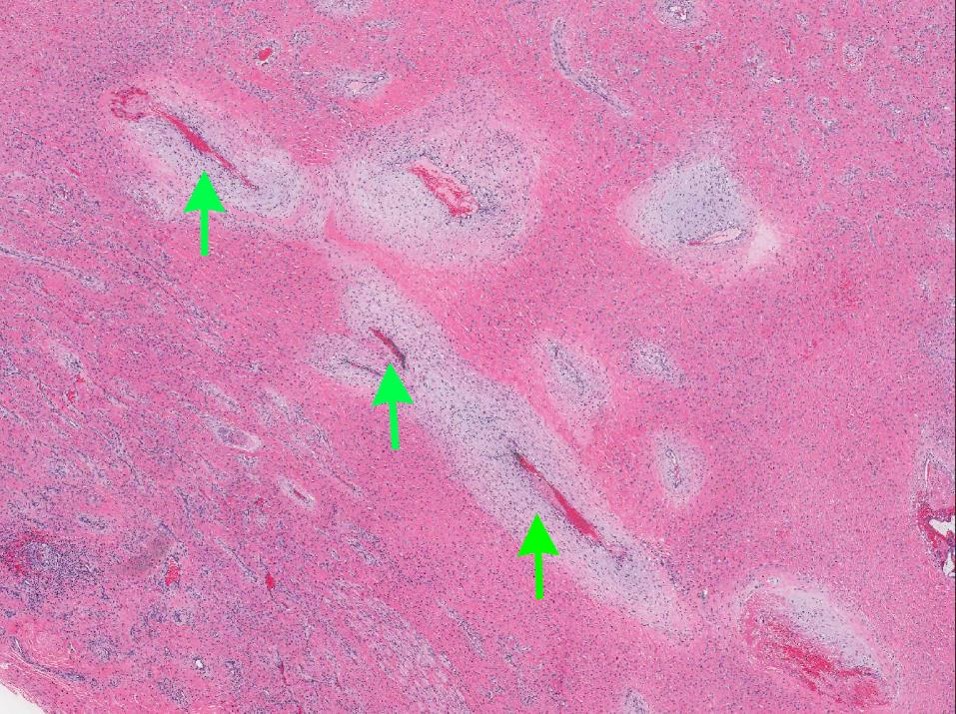

Microscopic (histologic) description

- Benign fibrovascular lesion composed of 2 components

- Vascular space of various sizes, ranging from dilated branching vessel of various thickness to slit-like capillaries

- Fibrous or collagenous stroma with fibroblasts

- Central area of the tumor is typically cellular, composed of fibroblasts or myofibroblasts with spindle, round or stellate morphology

- Stroma can be fibrous, edematous or collagenized

- Fibrinous thrombi may be seen in dilated vessels

- Frequently contain (abundant) mast cells

- Mitotic figures are usually absent

- Reference: Chan: WHO Classification of Head and Neck Tumours, 4th Edition, 2017